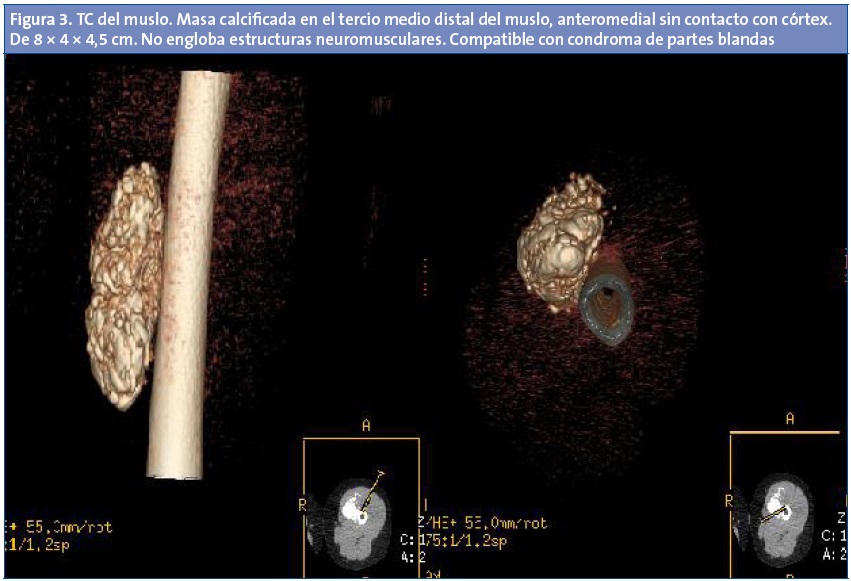

Ante los hallazgos clínicos se solicita radiografía simple del fémur izquierdo (Fig. 1) que evidencia una masa calcificada. Posteriormente se solicita ecografía del muslo (Fig. 2), que pone de manifiesto una imagen oval con múltiples imágenes hiperecogénicas en su interior que provocan sombras acústicas posteriores, lo que no sugiere un diagnóstico definitivo. Para concretar el diagnóstico se solicita una tomografía computarizada (TC) (Fig. 3), que pone de manifiesto una masa calcificada que no engloba estructuras neuromusculares, de características aparentemente benignas, pero que no permite descartar que se trate de un condroma de partes blandas.

La TC y la resonancia magnética (RM) muestran, con mayor resolución que la ecografía, las relaciones de la tumoración y la infiltración de estructuras vecinas. Pero algunos patrones pueden hacerla indistinguible de sarcomas de partes blandas u osteosarcomas.